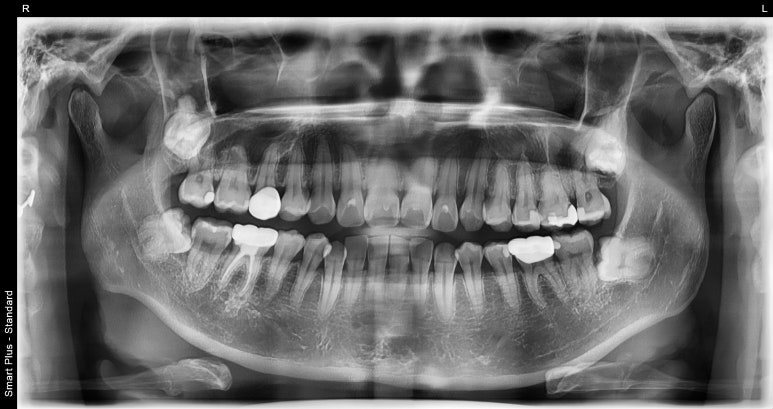

우선 잇몸성형을 위해 치과에 내원해주시면 잇몸뼈의 위치를 확인하기 위해 파노라마 엑스레이 촬영을 하게 됩니다.

잇몸뼈 위치 확인을 위한 파노라마 엑스레이

잇몸성형을 할 때는 잇몸뼈(치조골)의 위치를 파악해 뼈에 영향이 없도록 해야하기 때문입니다.